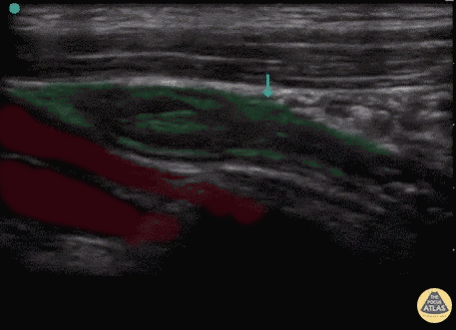

Appendix Red: Iliac vessels, Green: Appendix Images: Dr. Lindsay Davis, Dr. Hannah Kopinski. Image Editing: Michael Amador and Dr. Matthew Riscinti